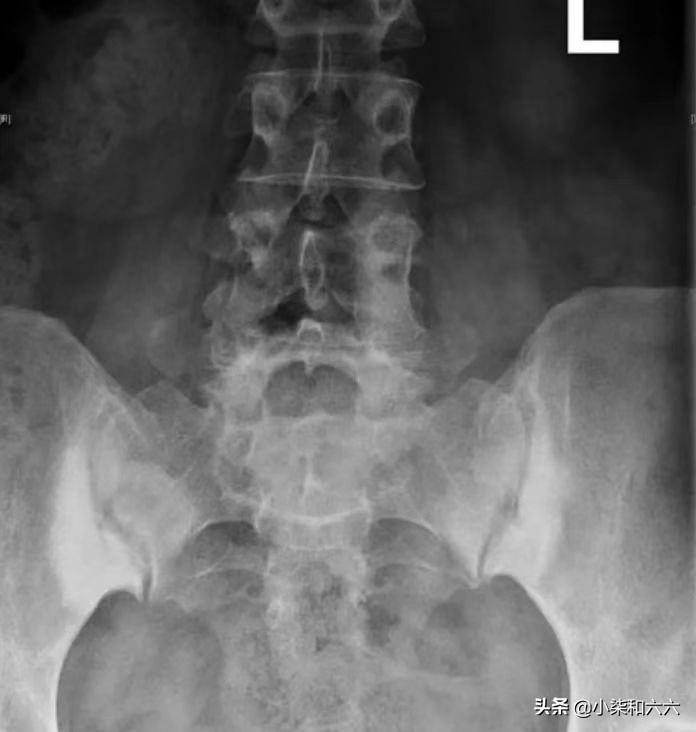

临床上通常以慢性下腰痛或骶髂关节区不适、间歇性酸痛、隐痛为主,多为一侧性,严重者常伴有髋关节活动障碍,且疼痛会向臀部、大腿背侧放射,步行、久坐、久站、负重及劳累后症状会加重。骶髂关节及臀中肌压痛明显,骨盆挤压及分离试验、4字试验阳性。放射学特征为骶髂关节的髂骨侧硬化,通常为双侧、对称和三角形,硬化区轮廓分明且致密,主要位于前中三分之一处。

骶髂关节双侧髂骨部硬化、三角形征